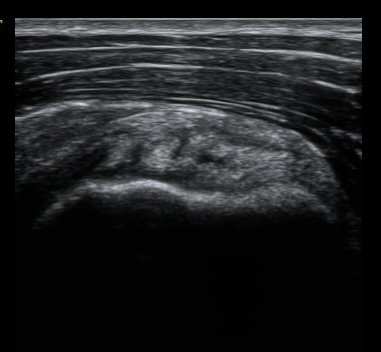

ȸÀü±Ù°³°£°Ý ³»Ãø Ⱦ´Ü¸é°Ë»ç¿¡¼­ °üÂûÇÑ °ß°©ÇÏ±Ù°Ç »óºÎ Á¾´Ü¸é°Ë»ç¿¡¼­ ¹Ì¼¼ÇÑ °£±ØÀÌ

°üÂûµÊ(±×¸² 3, 4). °ß°©ÇÏ±Ù°Ç È¾´Ü¸é°Ë»ç¿¡¼­µµ °ß°©Çϱٰdz» °£±ØÀÌ °üÂûµÊ(±×¸² 5).